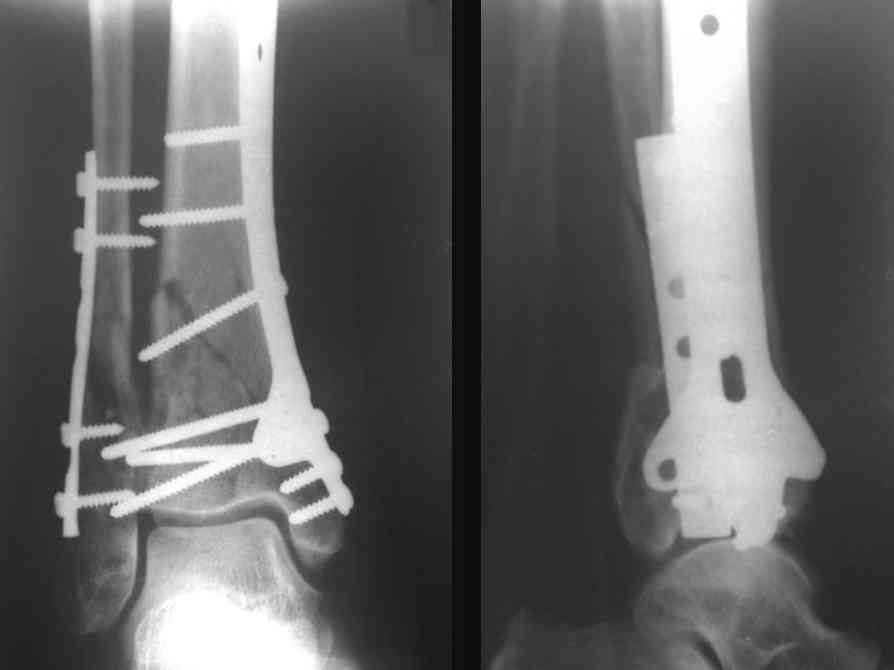

Посылаю результат лечения предыдущего больного через год.

С уважением Дрягин

Ja operiroval bolnogo po Vashemu, hotia sam ni ochen' ubezden' v itom, t.k. bolnoi otkazalsa na proch' ot ex.fix, ja emu sdelal ORIF + Kostnia plastika, snimky prelogiottsa,

Isskrenny Vash Castro